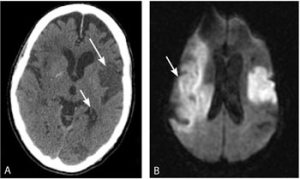

Figure 5

DWI (Label B) shows new Right MCA Territory Infarction not seen on CT (Label A):37

MRI Diffusion Weighted Imaging (DWI) can be obtained faster than conventional MRI, although like all MRI scans DWI has the disadvantage compared with CT of patient confinement (risk of claustrophobia) and less detail (in terms of thinness of slices).5 34 The DWI technique works on the principle that ischaemic cells have a different ability to handle water homeostasis compared with uninjured cells. DWI MRI can detect areas of acute ischaemia using a specific system based on the ‘apparent diffusion coefficient’ (ADC) of water.23 The associated subtle changes seen in Acute Stroke usually need to be interpreted by a senior radiologist which may be a disadvantage especially in remote locations and out of hours. Having said this, telemedicine using internet broadband may make advanced imaging more accessible in the future in Australia.35

In clinical practice DWI MRI increases diagnostic yield when compared with Plain CT (from 50% to >90%).5 This increased yield is illustrated in Figure 5 (below). This technique could be used as an alternative in patients who cannot have a CT perfusion study due to contrast allergy or chronic kidney disease. Additionally, a 2013 review by Oosteema et al suggested that DWI MRI may provide the ability to risk stratify TIA patients and hence discharge patients low risk patients from the Emergency Department.36 Finally, although the detection rates of infarction on CT and MRI are similar, the diagnostic yield of MRI in terms of identifying a clinically appropriate or clinically relevant lesion, is much higher. In other words, the ability to distinguish between acute and chronic infarction on MRI is important for the treating stroke team as it allows optimum management of the current problem.17